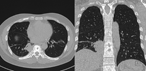

Disseminated Mycobacterium abscessus infection with spondylodiscitis of thoracic spine

Zhong Zhang and others

Journal of Surgical Case Reports, Volume 2018, Issue 6, June 2018, rjy141, https://doi.org/10.1093/jscr/rjy141